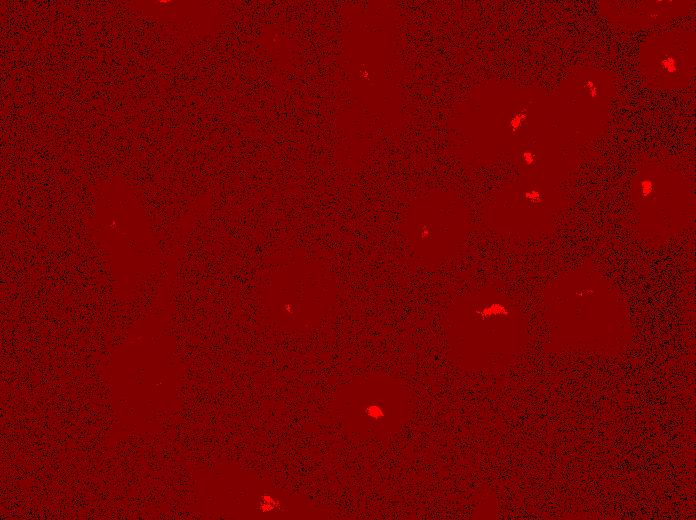

Golgi Apparatus

(anti-GM130)